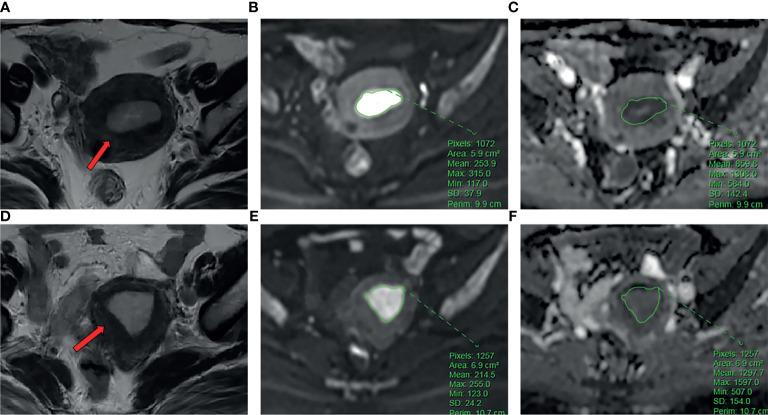

Clinical, pathological and MRI findings of 110 EC patients were analyzed retrospectively. The expression levels of Ki-67 and p53 in EC tissues were detected by immunohistochemistry. ADC value was calculated, and three-dimensional (3D) texture features were measured on T-weighted images (TWI), diffusion-weighted images (DWI), and contrast-enhanced T-weighted images (CE-TWI). The univariate and multivariate logistic regression and cross-validations were used for the selection of texture features. The receiver operating characteristic (ROC) curve was performed to estimate the diagnostic efficiency of prediction model by the area under the curve (AUC) in the training and validation cohorts.

Significant differences of the ADC values were found in predicting Ki-67 and p53 (=0.039, =0.007). The AUC of the ADC value in predicting the expression levels of Ki-67 and p53 were 0.698, 0.853 and 0.626, 0.702 in the training and validation cohorts. The AUC of the TA model based on TWI, DWI, CE-TWI, and ADC value combined with TWI + DWI + CE-TWI in the training and validation cohorts for predicting the expression of Ki-67 were 0.741, 0.765, 0.733, 0.922 and 0.688, 0.691, 0.651, 0.938, respectively, and for predicting the expression of p53 were 0.763, 0.805, 0.781, 0.901 and 0.796, 0.713, 0.657, 0.922, respectively.